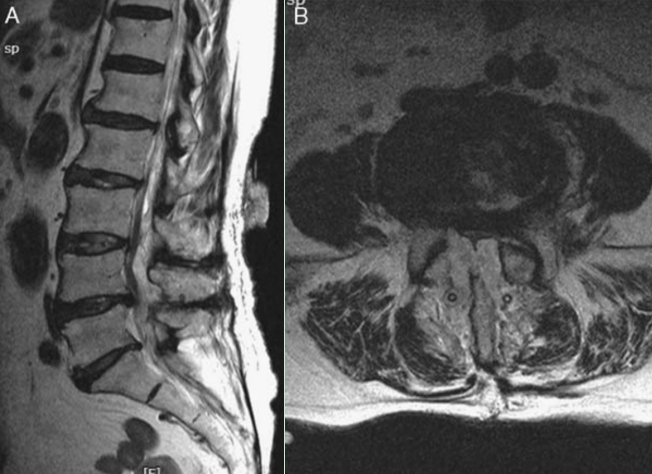

图1 MRI显示腰椎术后SEH形成

血肿形成是腰椎术后早期严重并发症,一般发生在术后1~2d,符合手术指征者应当立即探查切口、清除血肿。血肿一般位于手术切口部位,部分无症状患者血肿可自行吸收,而一些患者则表现为切口剧烈疼痛,若压迫神经还可出现肌力下降和感觉减退,但因血肿部位不同,神经损伤表现也有所不同。其中硬膜外血肿(spinal epidural hemorrhage,SEH)进展迅速,对脊髓压迫时间越长,脊髓损伤越重,严重者可导致瘫痪。

除SSI外,SEH也是脊柱退行性疾病URP的主要原因。Shimizu等发现9335例脊柱退行性疾病患者中有33例因SEH再次手术。Zijlmans等报道1333例腰椎退行性疾病患者接受单节段或双节段腰椎间盘切除术或腰椎板切除术,术后2例发生SEH,并伴随明显神经功能损伤,因此再次手术清除血肿。Yi等对3720例患者临床资料进行回顾性研究,发现3例腰椎管狭窄症和1例腰椎间盘突出症患者因SEH严重损伤神经再次手术。Aihara等调查了394例显微内镜腰椎减压手术患者,发现3例因SEH再次手术。Snopko等调查了371例腰椎退行性疾病患者,发现7例减压手术后因SEH再次手术。Mueller等以1 004例腰椎退行性疾病患者为研究对象,行微创腰椎椎板切除术或椎板切开术进行减压后,有14例因SEH再次手术,其中9例神经功能受损。Tsai等提出,相比于其他并发症,SEH更易导致神经损伤,其研究中10 350例患者有27例因SEH合并神经损伤再次手术,其中20例术后神经功能得到改善,但仍有7例未改善。Khalifa等的研究共纳入51例接受腰椎融合术的患者,发现2例因皮下血肿再次手术。

此外,目前已经证实输血、多节段手术和肥胖是SEH的危险因素。也有学者提出抗凝剂、术前凝血值异常和吸烟是脊柱术后SEH的独立危险因素。